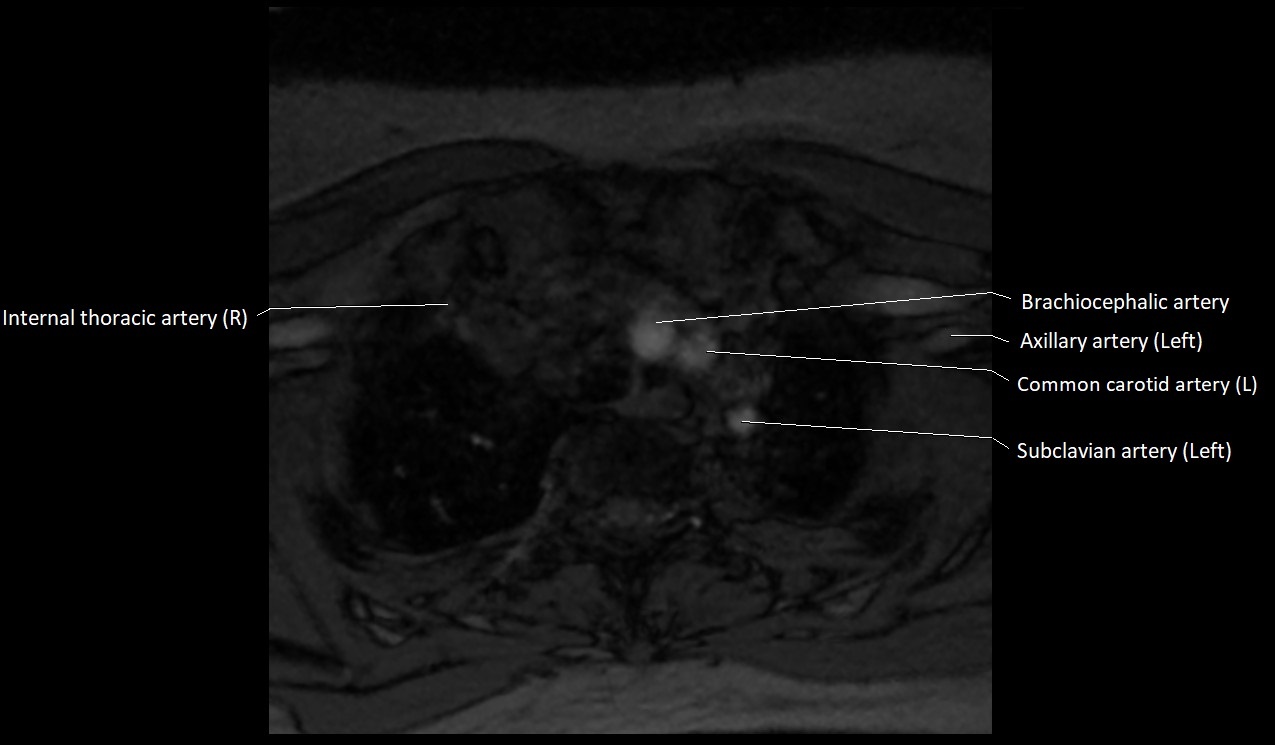

MRI images

image